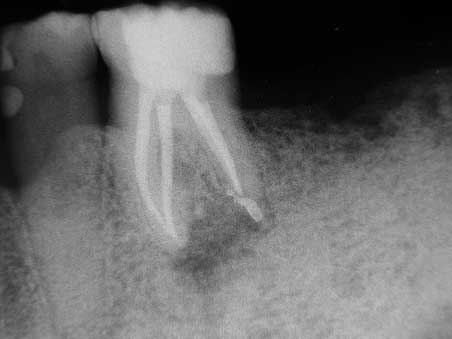

Apikale Aufhellung 001 Bild 5

Veröffentlicht 10. Februar 2009 am 452 × 339 in Apikale Aufhellung (1)